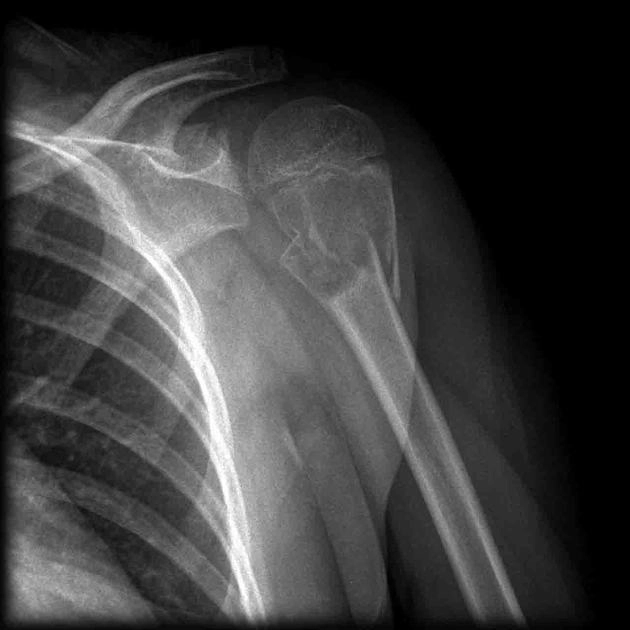

U tế bào khổng lồ của xương (Giant Cell Tumor - GCT of bone)